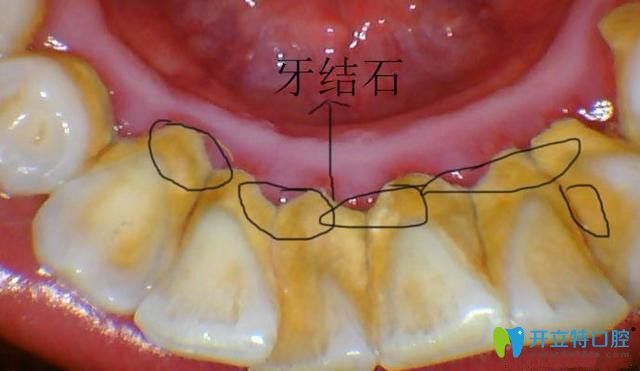

所以超聲波潔牙是可以去除牙斑菌、牙結(jié)石,又要的預(yù)防牙周炎、牙齦炎等口腔疾病,是很好的牙齒護(hù)理方法,對(duì)牙齒無(wú)害。

超聲波去牙結(jié)石